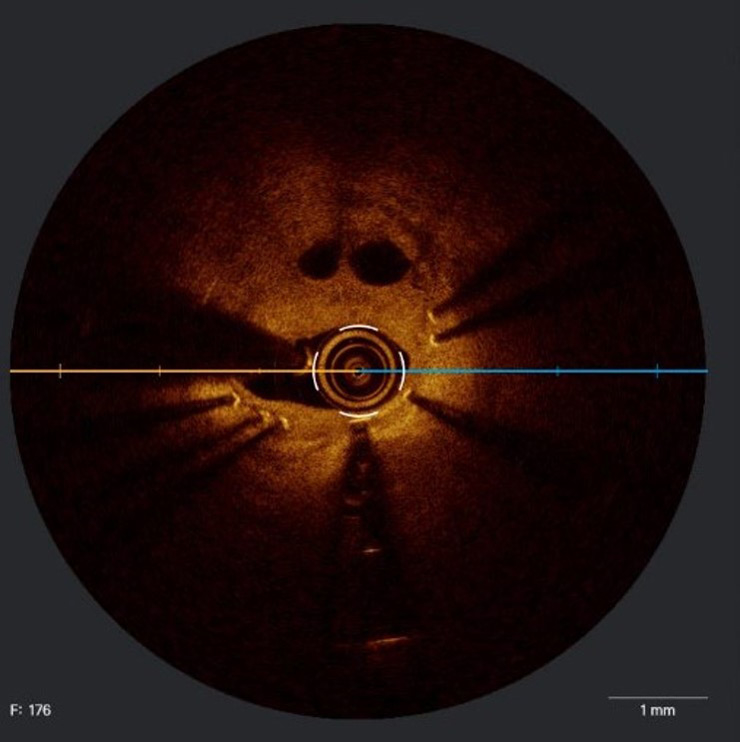

What is this "ghost-in-situ" in this OCT run?

This is an OCT run taken from a stent placed in RCA six years back in a 74-year-old male who presented with NSTEACS. The run has been taken without predilatation.

ISR requires a mechanistic approach and the neointimal tissue characteristics as elaborated by OCT may tailor our approach to PCI in ISR.